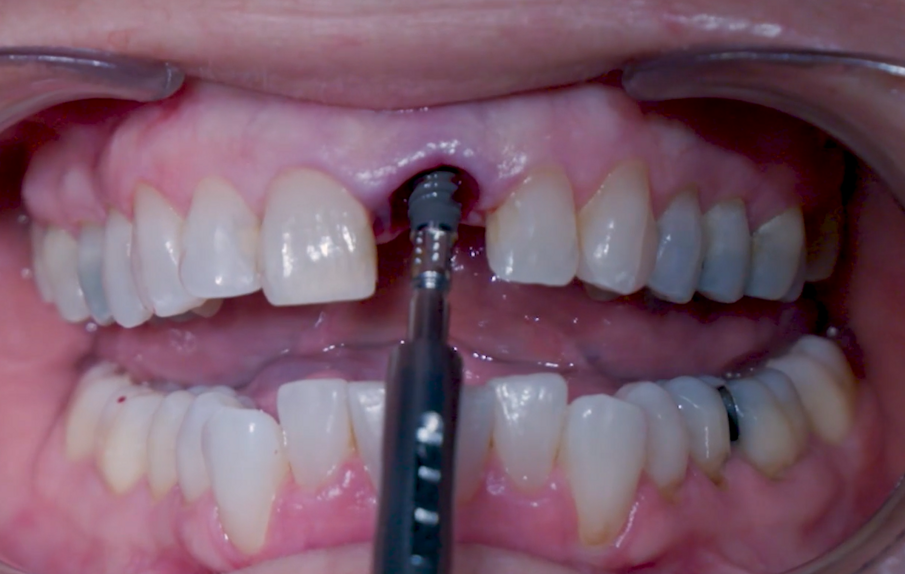

Dopo l’inserimento, la posizione dell’impianto è stata verificata orizzontalmente con uno specchio occlusale e verticalmente con una sonda chirurgica e a questo punto è stata selezionata l’altezza gengivale dell’abutment (Figg. 11, 12). Un abutment di guarigione è stato posizionato sull’impianto (Fig. 13) per proteggere la connessione in modo che l’osseo granulare sostitutivo (Straumann XenoFlex) potesse essere applicato nella fessura tra l’impianto e la parete vestibolare. Questo è stato delicatamente compattato con il lato di 2,8 mm della sonda chirurgica (Figg. 14–16). Il Collacone (biomateriali botiss) è stato utilizzato per tenere i granuli ossei lontano dai margini gengivali, allo scopo di evitare la fenestratura dei tessuti molli e l’infiltrazione fibroblastica (Figg. 17, 18).

Fig. 11_Valutazione finale della posizione dell'impianto.

Fig. 12_Valutazione finale della posizione dell'impianto in relazione ai margini gengivali.

Fig. 13_Vite di guarigione per proteggere l’abutment.